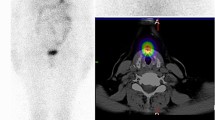

Robbins, R. J. et al. Real-time prognosis for metastatic thyroid carcinoma based on 2-[18F]fluoro-2-deoxy-D-glucose-positron emission tomography scanning. J. Clin. Endocrinol. Metab. 91, 498–505 (2006).